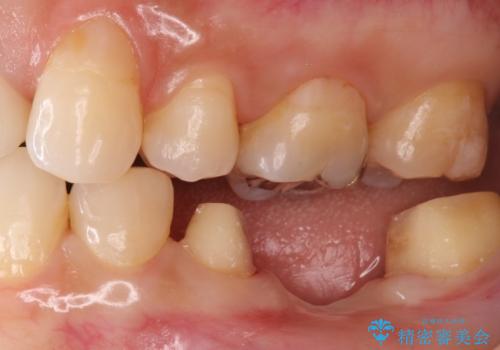

- 左下の銀歯の状態が悪く抜歯してブリッジにした患者様です。

抜歯してからブリッジの仮歯をすぐ入れるため、歯がない期間はほとんどありません。

途中全体矯正をはさみ、根の向きが並行になった状態でブリッジを入れることができました。